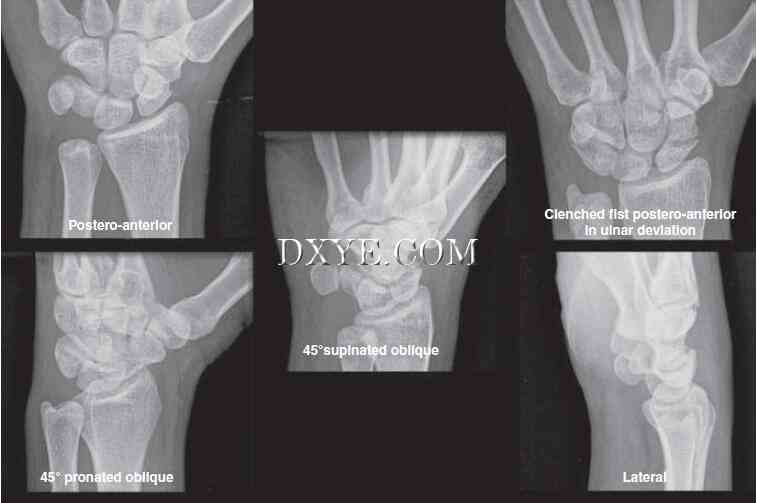

前后位(PA)和侧位片是常规的。 PA视图是在90°外展的肩部,90°屈曲的肘关节以及中立旋转的手腕和前臂的情况下获得的(图76.3A)。 在一个真正的PA标准视图中,尺侧腕伸肌腱的沟槽应位于尺骨茎突基部的水平或径向(图76.3B)。 肩关节90°内收,肘关节屈曲90°,手与肱骨相同(图76.4A)。 在真正的侧面图中,豌豆皮的掌侧皮层应覆盖远侧舟骨掌侧皮质和头状体头部之间的中间三分之一(图76.4B)。

三影像学测量标准的PA和侧视图与患者的预后相关:径向高度、径向倾斜,和掌倾角(图76.5)。桡骨高度在PA片作为一个垂直的半径通过乙状切迹远端的尺骨远端关节面半径的长轴在桡骨茎突尖第二垂直线之间的距离测量。正常径向高度平均为10至14毫米。桡骨关节面有桡尺坡(径向倾角)和背向掌侧坡(掌侧倾斜)。

在PA射线照片上也测量径向倾斜,并且表示连接桡骨茎突的尖端和远侧半径的尺骨方向的一条线与垂直于半径的纵向轴线的第二线之间的角度。 正常的径向倾角在20°和25°之间。 手掌倾斜度是在侧位X线片上测量的,代表了沿着半径的远端关节面的线与垂直于半径的纵轴线的线之间的角度。 正常手掌倾斜平均11°,范围5°至15°。 有用的附加射线照相参数是尺骨方差。 尺骨方差是指尺骨头的关节面与月骨的尺骨边界之间的距离。 当两者都处于同一水平时,它被描述为中性:尺骨加上尺骨长的时候; 和尺骨减去尺骨短的时候(图76.6)。 正常尺骨方差的范围可以从0±2毫米。

5.jpg

图 76.5.  桡骨远端[径向高度的影像学参数测量(红色虚线),径向倾角(白色虚线),和掌倾角(绿色虚线)]。

6.jpg

图 76.6.  测量尺骨方差。

影像学评估。 除了标准的PA和手腕的侧面视图之外,还应该获得45°前倾斜视图和PA握拳尺度偏差(图76.20)。 尺骨的偏差使舟骨处于延伸的姿势,并使其更加完整。 紧握的拳头会突出任何一个舟骨函数扩大和分散任何不稳定的骨折片段。